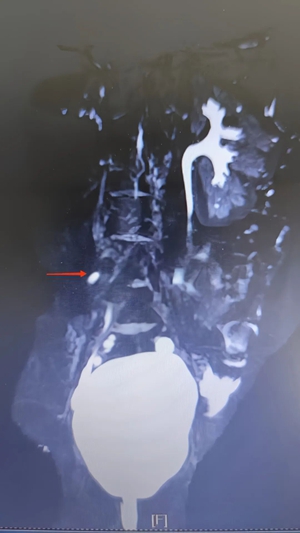

接诊后,小儿泌尿外科主任高强凭借丰富的临床经验,并未将小玉的症状简单归为排尿控制能力差。结合患儿长期漏尿的病史,医生为小玉完善了超声、MRI 尿路成像(MRU)、CT 等一系列检查,最终明确诊断为右肾发育不良伴输尿管异位开口。

单侧肾发育不良示意图

输尿管异位开口示意图